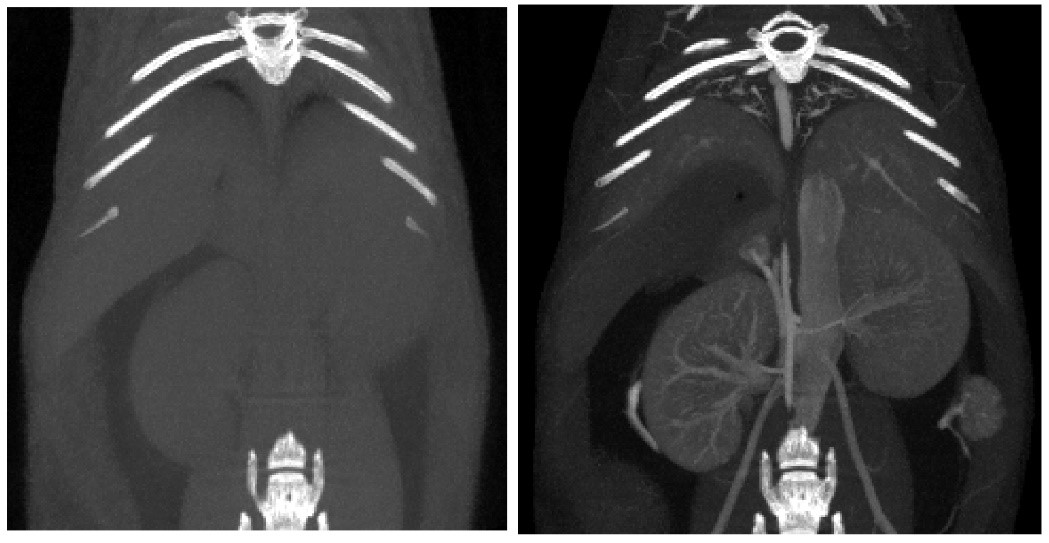

Contrast-enhanced CT:

對比增強CT.jpg

(5) Angiography: The developer is rapidly injected into the heart cavity or blood vessel through the cardiac catheter, so that the heart and blood vessel cavity can be developed under CT irradiation. Using contrast media CT, the vascular system and blood-rich tissues and organs can be shown. Ranging from arteries to heart, lungs, kidneys, liver, etc. Provides a better soft tissue contrast for sharper imaging.

6、Contrast-enhanced tumor CT imaging

Tumor study: Contra-enhanced CT was used to examine liver tumors in living mice: Exitron 12000 was injected, FDK was reconstructed, and the imaging time was 4min, 100μm voxel size.